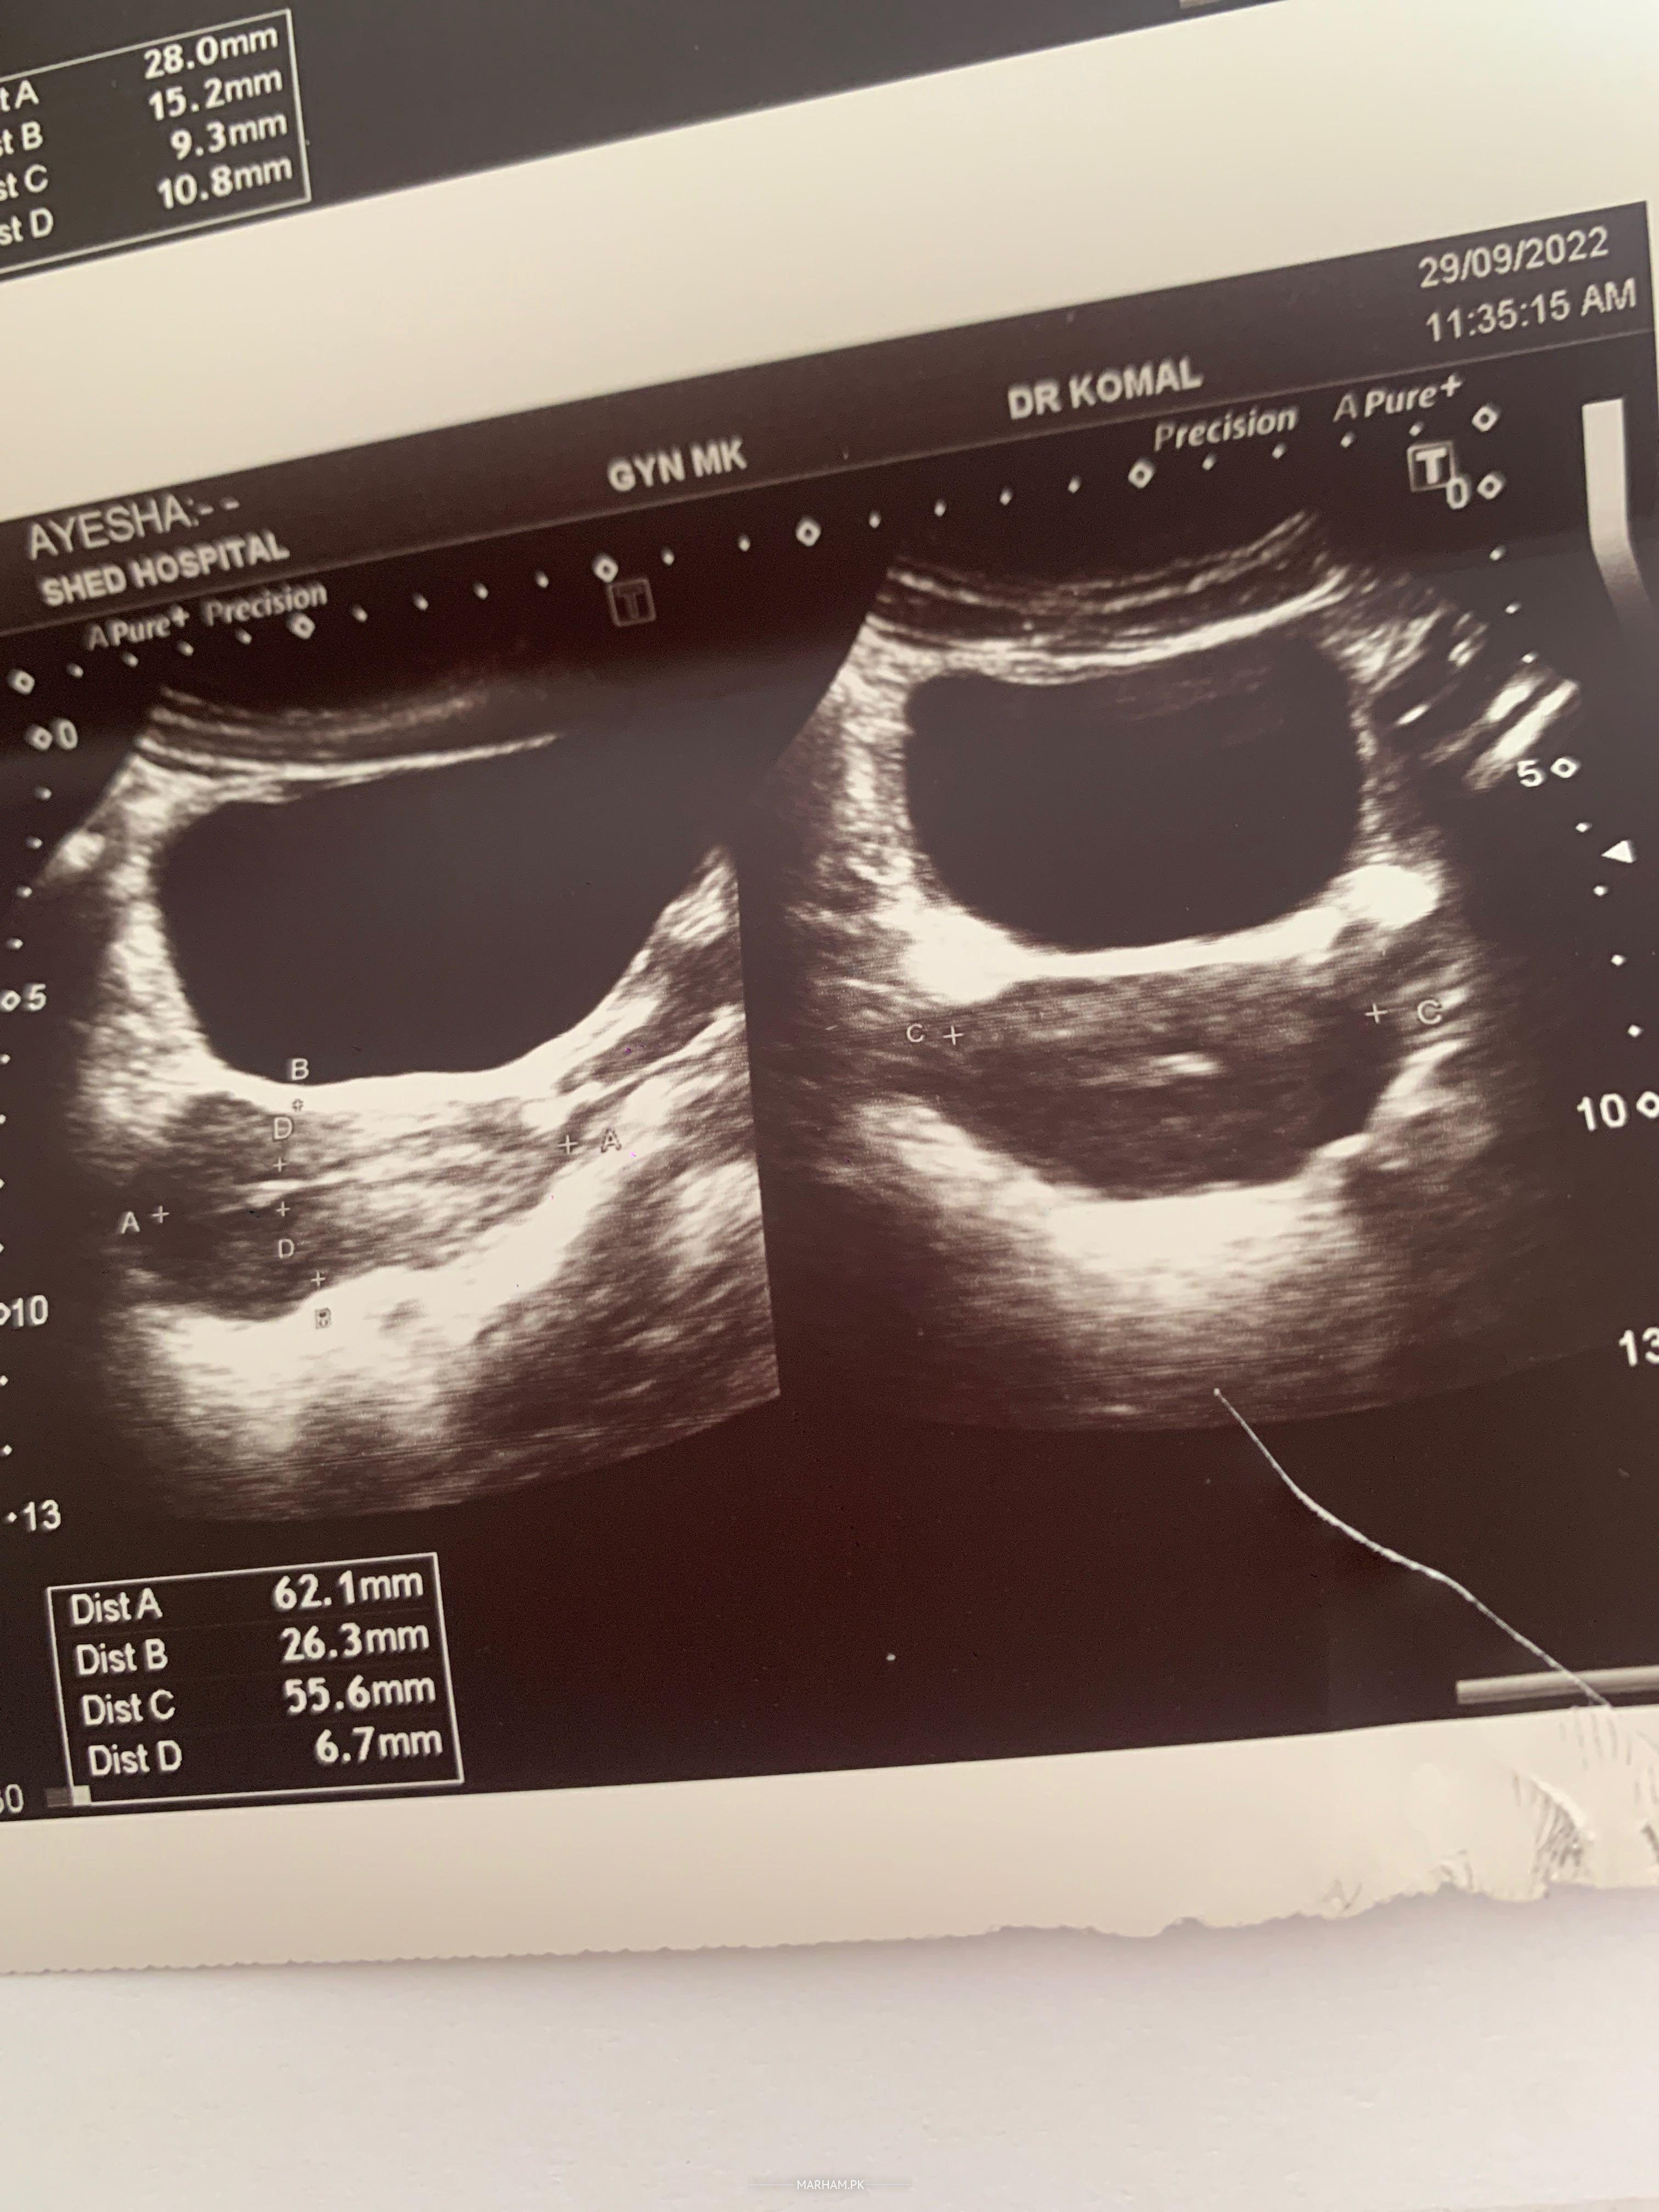

Kindly check my report and reply I’m in tension why is issue? Thankyou

Attach Photo here: